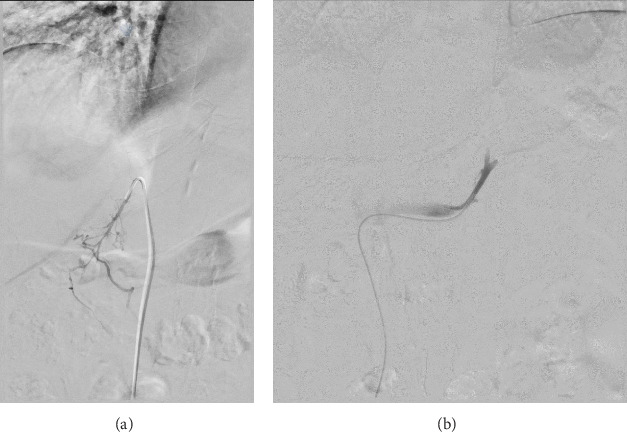

We report a case of successfully lateralized adrenal cortisol hypersecretion by adrenal venous sampling (AVS) and improved by surgery. AVS is a commonly used tool to guide surgical management of primary hyperaldosteronism. It can determine lateralization, leading to unilateral adrenalectomies of the correct side, or nonlateralization, which precludes surgery. The use of AVS in determining lateralization in hypercortisolism is a growing field of discussion. Currently, there is no defined or unanimous protocol behind procedural details and interpretation of results. In this report, we describe the AVS protocol at our institution for hypercortisolism, interpretation of the results, and corresponding surgical outcomes for a case of mild autonomous cortisol secretion.

Abstract Image